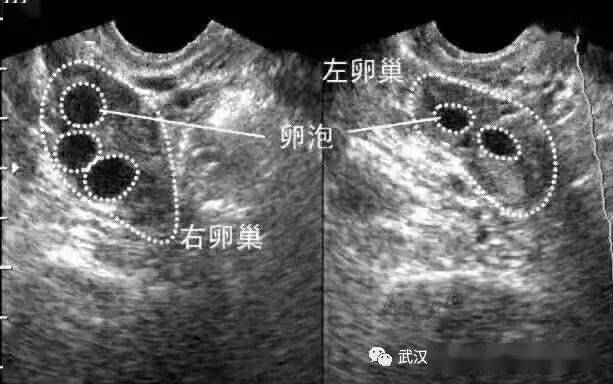

看准了!卵泡"优等生"长这样_排卵_mm_杭州

形,壁薄,透声好,向卵巢一侧突出,只有达到这样的好"卵泡",才可排卵